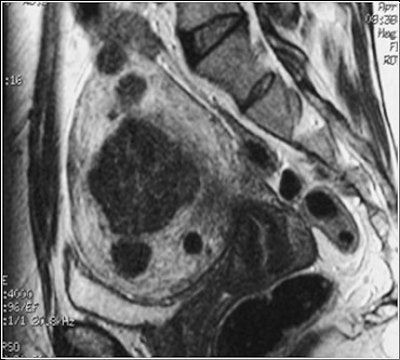

![]() |

| The same patient six months after the UFE procedure. This sagittal, T1-weighted midline MR image shows a 50% decrease in the size of the uterus (white arrow). The fibroids have low signal (black arrow), consistent with devascularization. The patient reported complete relief of symptoms. Image courtesy of Dr. Steven Janney Smith. |